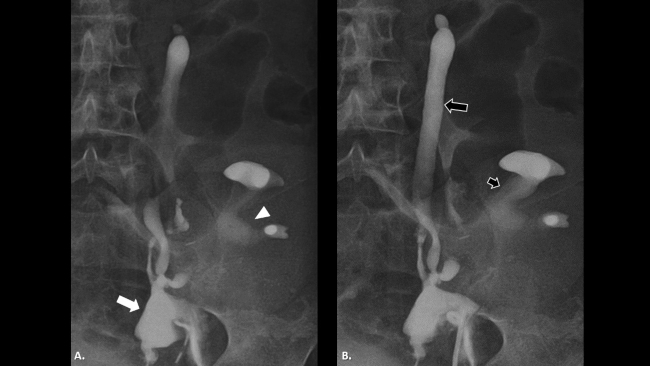

En la actualidad, la ureteropielografía ascendente (►Fig. 4) se encuentra mayormente fuera de uso para el diagnóstico de esa patología, aunque podría llegar a ser un método diagnóstico para certificar el cuadro patológico, demostrando en la mayoría de los casos el uréter remanente dilatado, de morfología lobulada y en algunos casos evidenciar reflujo vesicoureteral como punto de partida de la enfermedad.

Fistulografía en paciente con riñón trasplantado en fosa ilíaca izquierda. (a) Colección periureteral (flecha blanca) por delante del riñón trasplantado (cabeza de flecha). (b) Dilatación del muñón ureteral en todo su trayecto (flecha negra) y dilatación del sistema uroexcretor del riñón trasplantado (flecha negra corta).